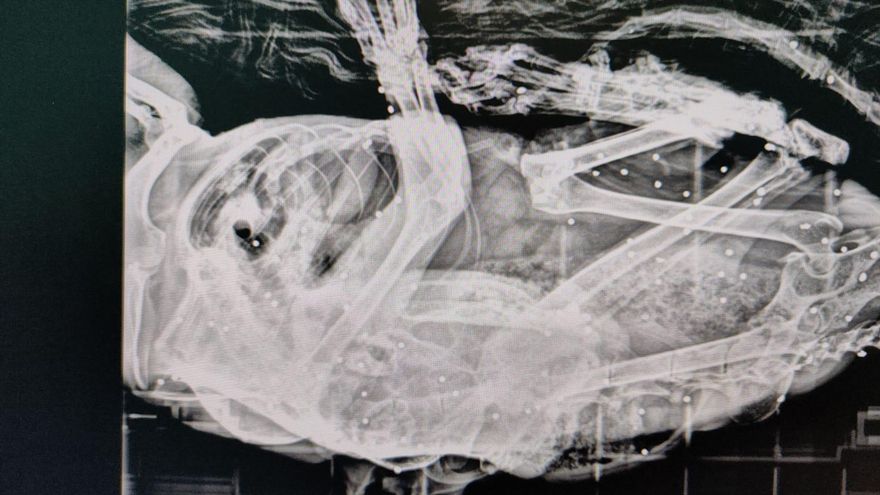

Prueba radiológica del gato con perdigones en su interior

Se trata de Van Gogh, un animal que había sido intervenido quirúrgicamente por un carcinoma en la oreja y se encontraba recuperándose en el refugio cuando comenzó a mostrar cojera persistente. Tras su traslado al veterinario y la realización de pruebas radiológicas, se detectaron los perdigones en su interior.